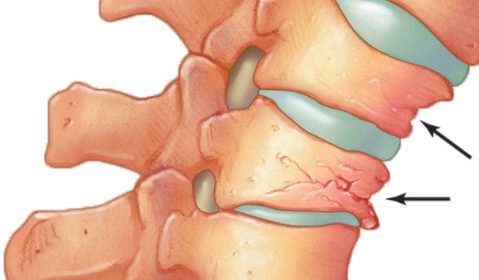

椎體成形術俗稱打骨水泥,是以針孔微創的手術,把人造骨粉(丙烯酸膠粘劑)注射到脊椎椎體骨折下陷的地方,強化並鞏固因骨質疏鬆導致脆弱的骨骼,重建椎體的骨骼形狀以防止下陷前傾的骨椎進一步惡化(見圖二至五)。適合進行椎體成形術的情況包括(1)因骨折造成的持續腰背痛;(2)因嚴重骨質疏鬆致骨骼脆弱,脊骨前傾及出現駝背現象;(3)任何藥物都起不了作用。這項小手術只須一小時的時間,病人可在術後24小時回家,不須再服止痛藥,但須服用抗骨質疏鬆藥物,來預防脊椎、盤骨或其他部位骨折及下陷。

圖二

圖三

椎體成形術是以針孔微創的手術,注射人造骨粉(丙烯酸膠粘劑)到脊椎椎體